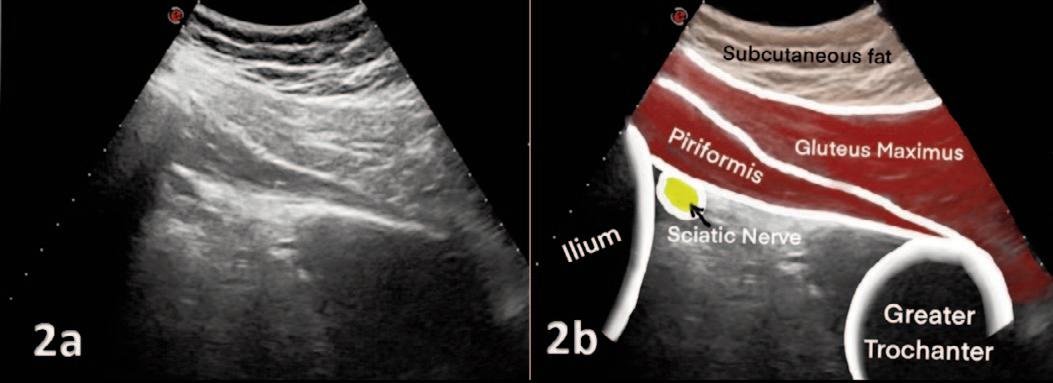

768 Use of Diagnostic Musculoskeletal Ultrasound in the Evaluation of Piriformis Syndrome: A Review for Rehabilitation Providers.

Manske RC, Wolfe C, Page P, Voight M, Bardowski B.